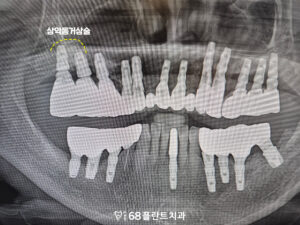

먼저 치아를 발치한 후

오른쪽 위는 상악동거상술을 진행하며

상악동 내부에 뼈가 부족한 부분을

보충하기 위해 뼈 이식을 실시했습니다.

이후, 충분히 시간이 지난 후,

임플란트 식립을 진행하여

보다 견고한 결과를

얻을 수 있도록 했습니다.

롱브릿지 부분도 임플란트를 식립하여

기존의 브릿지가 받던 하중을

분산시킬 수 있도록 했습니다.